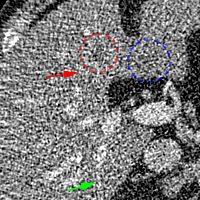

To show the denoising effect of the selected networks, we took two representative slices as shown in Figs. 5 and 7. And Figs. 6 and 8 are the zoomed regions-of-interest (ROIs) marked by the red rectangles in Figs. 5 and 7. All the networks demonstrated certain denoising capabilities. However, CNN-MSE blurred the images and introduced waxy artifacts as expected, which are easily observed in the zoomed ROIs in Figs. 6e and 8e. WGAN-MSE was able to improve the result of CNN-MSE by avoiding over-smooth but minor streak artifacts can still be observed especially compared to CNN-VGG and WGAN-VGG. Meanwhile, using WGAN or GAN alone generated stronger noise (Figs. 6g and 8g) than the other networks enhanced a few white structures in the WGAN/GAN generated images, which are originated from the low dose streak artifact in LDCT images, while on the contrary the CNN-VGG and WGAN-VGG images are visually more similar to the NDCT images. This is because the VGG loss used in CNN-VGG and WGAN-VGG is computed in a feature space that is trained previously on a very large natural image dataset [48]. By using VGG loss, we transferred the knowledge of human perception that is embedded in VGG network to CT image quality evaluation. The performance of using WGAN or GAN alone is not acceptable because it only maps the data distribution from LDCT to NDCT but does not guarantee the image content correspondence. As for the lesion detection in these two slices, all the networks enhance the lesion visibility compared to the original noisy low dose FBP images as noise is reduced by the different approaches.

As for iterative reconstruction technique, the reconstruction results depend greatly on the choices of the regularization parameters. The implemented dictionary learning reconstruction (DictRecon) result gave the most aggressive noise reduction effect compared to the network outputs as a result of strong regularization. However, it over-smoothed some fine structures. For example, in Fig. 8, the vessel pointed by the green arrow was smeared out while it is easily identifiable in NDCT as well as WGAN-VGG images. Yet, as an iterative reconstruction method, DictRecon has its advantage over post-processing method. As pointed by the red arrow in Fig 8, there is a bright spot which can be seen in DictRecon and NDCT images, but is not observable in LDCT and network processed images. Since the WGAN-VGG image is generated from LDCT image, in which this bright spot is not easily observed, it is reasonable that we do not see the bright spot in the images processed by neural networks. In other words, we do not want the network to generate structure that does not exist in the original images. In short, the proposed WGAN-VGG network is a post-processing method and information that is lost during the FBP reconstruction cannot easily be recovered, which is one limitation for all the post-processing methods. On the other hand, as an iterative reconstruction method, DictRecon algorithm generates images from raw data, which has more information than the post-processing methods.